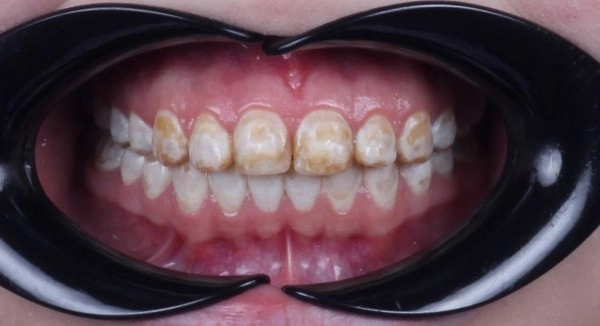

Как проявляется флюороз: ⠀⠀

Зубная эмаль утрачивает блеск.⠀

Появляются пятна и полоски, как правило, на передних резцах верхней челюсти. В зависимости от стадии течения болезни цвет колеблется от беловато-серого до коричневого.⠀

Зубы начинают болезненно реагировать на холодную и горячую пищу и жидкость.⠀

Зубы в местах пигментации становятся хрупкими, склонными к сколам и разрушению.⠀

На фото работа врача стоматолога - ортопеда Сергеевой Анастасии Сергеевной.